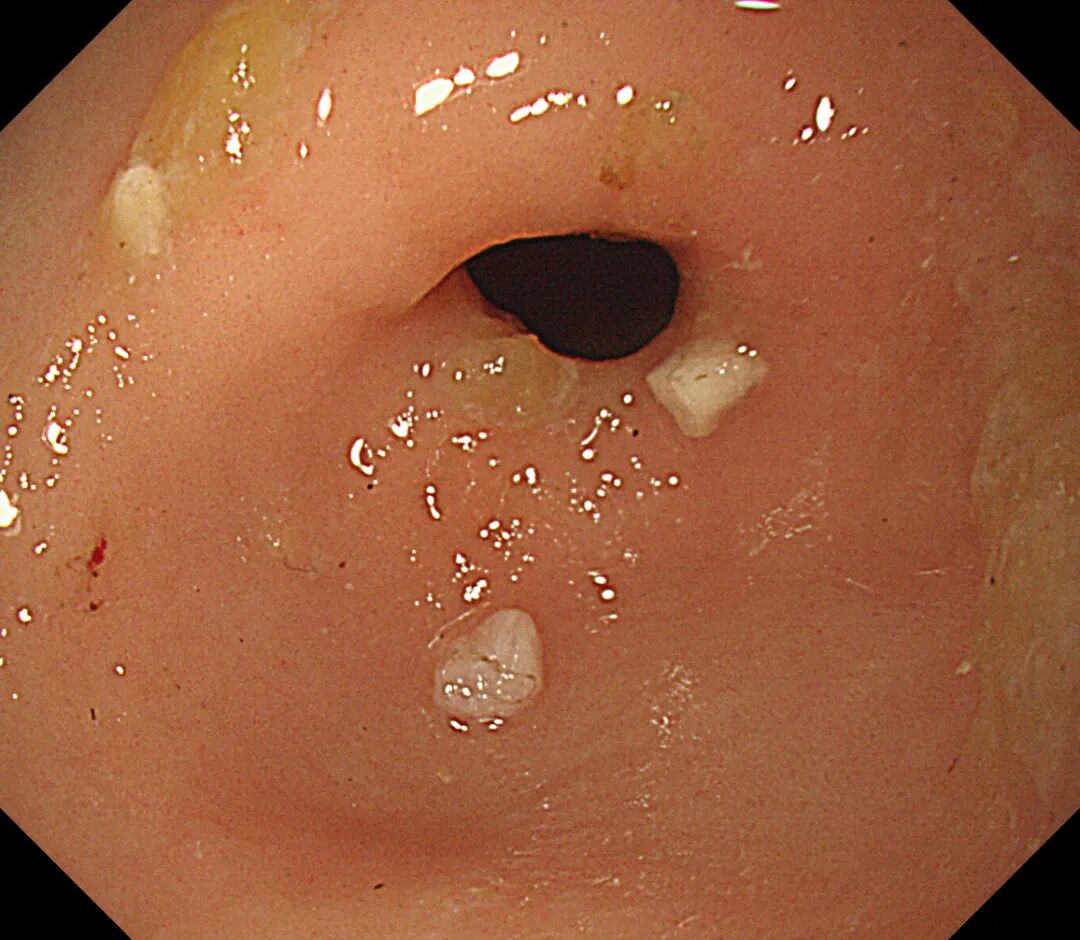

如何将风险降到最低,宜宾市中医医院立即开通绿色通道,多科协作,经讨论决定选择对娃娃损伤最小的全麻下经胃镜行消化道异物取出术。术中在胃镜下见4枚铁钉嵌顿于幽门口,随时有排入十二指肠的风险,立即予异物钳夹取,整个操作过程娴熟、流畅,成功将4枚铁钉完整取出。

4枚铁钉嵌顿于幽门口